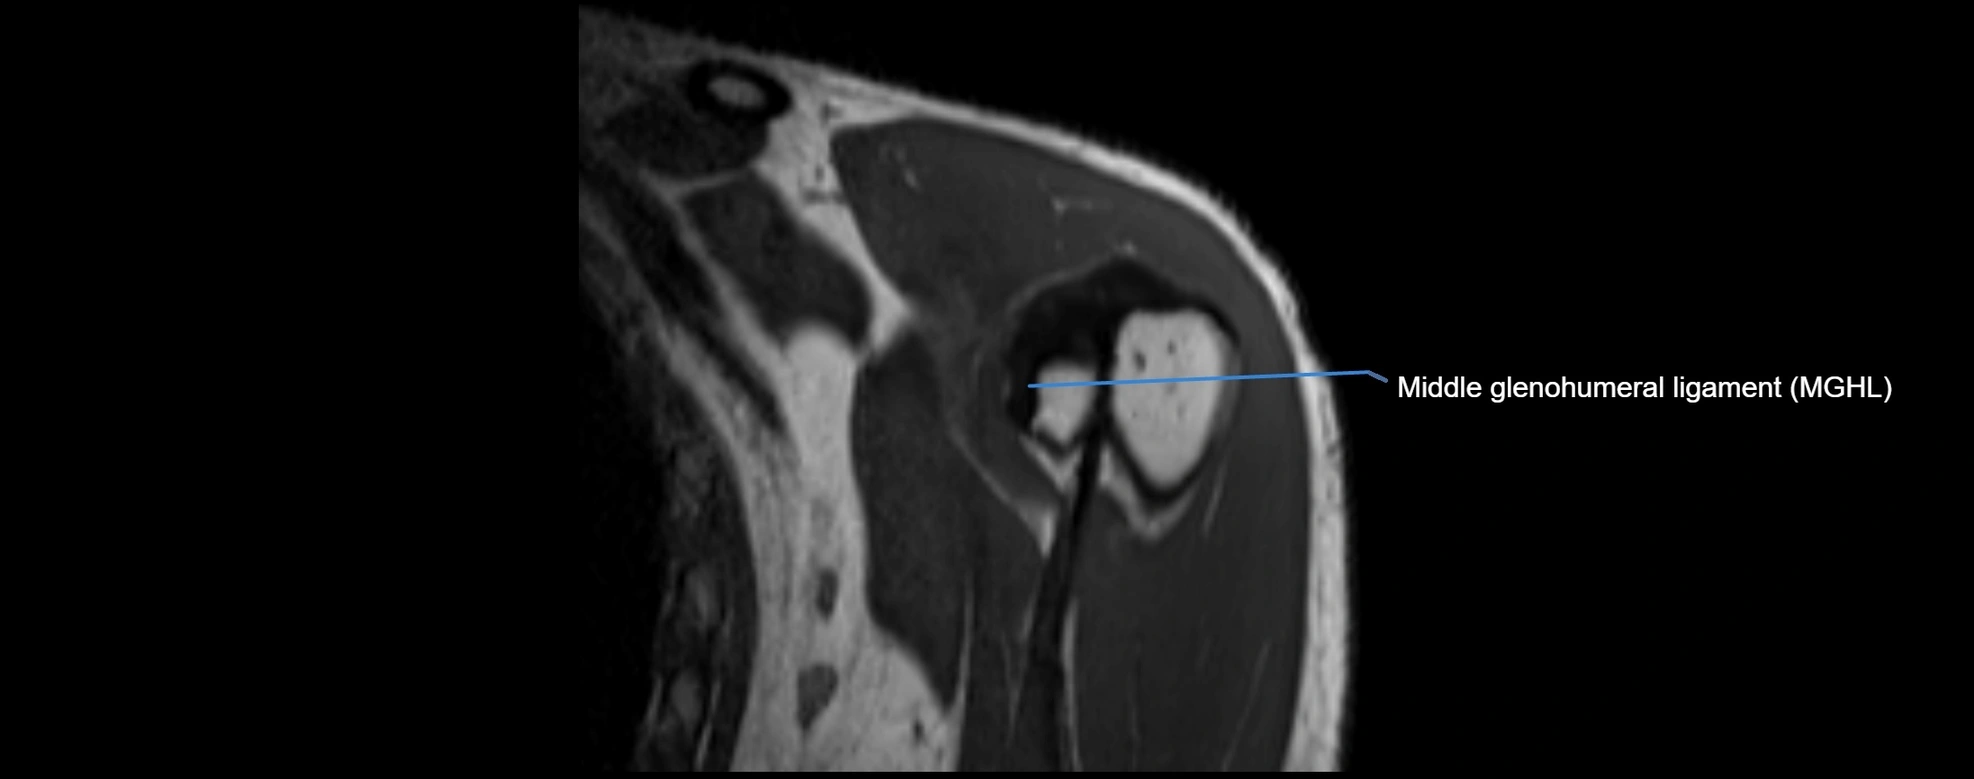

MRI Appearance

• T1-weighted images:

• Normal ligament: Low signal (dark linear band) spanning acromion to clavicle.

• Surrounding fat planes: Bright, delineating the ligament clearly.

• Marrow of clavicle and acromion: Bright due to fatty content.

• Tears: Discontinuity or irregular thickening with intermediate-to-bright signal.

• Chronic injury: Thinning, fraying, or irregular low-signal fibers with adjacent scarring.

• T2-weighted images:

• Normal ligament: Low signal, homogeneous.

• Partial tear or sprain: Focal hyperintensity or thickening.

• Complete tear: Discontinuity with fluid-bright gap between clavicle and acromion.

• Associated edema: Bright signal in distal clavicle or acromion marrow.